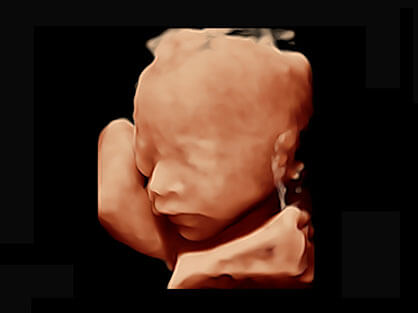

• 产科自动测量

自动获取标准切面,自动完成测量,帮助医生快速完成检查,同时提升测量准确性。

• AVC Follice卵泡自动测量

卵泡结构的自动识别和测量,可显示多组测量数据。